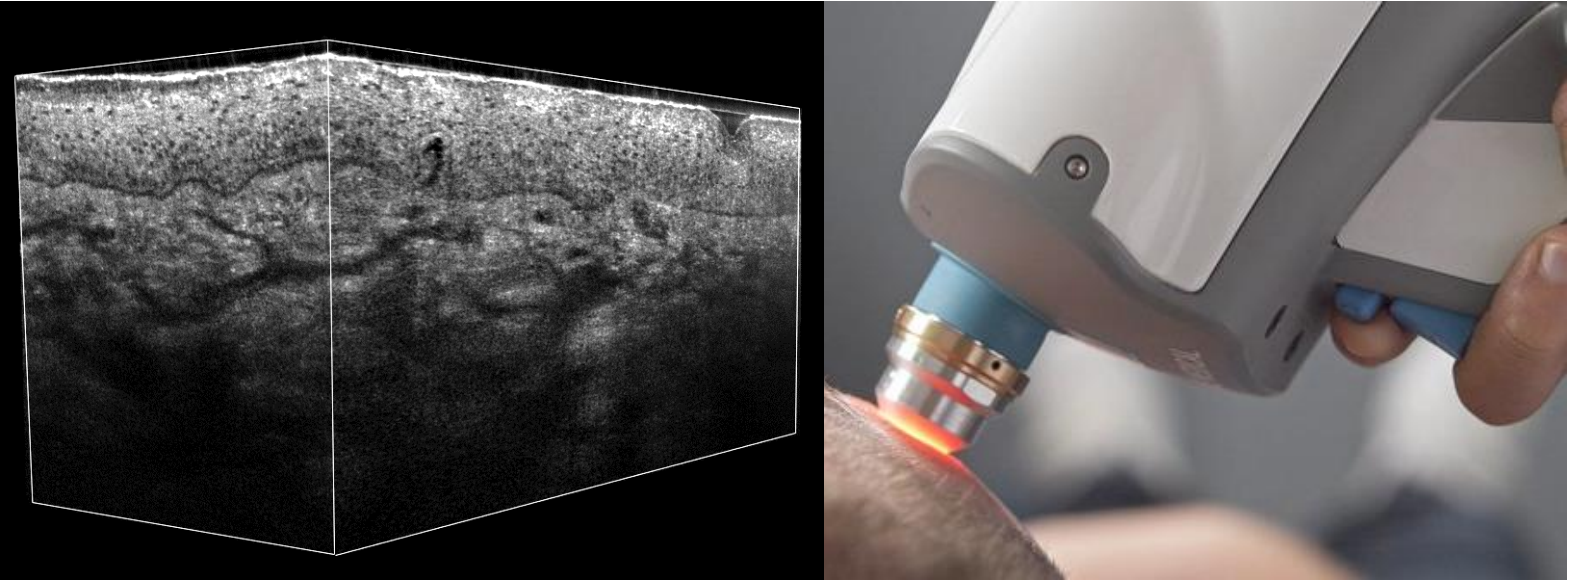

The system enables four imaging modes: vertical, horizontal, or combinations of both to create 3D reconstructions. In practice, the system combines horizontal images because it allows more control over volume reconstruction. It also presents a more direct path to future improvements in acquisition speed. The system currently acquires vertical and horizontal images at a live rate of 8 fps and can reconstruct 1.2 × 0.5 × 0.5 mm3 image volumes with nearly isotropic 1 µm resolution.

These principles are applicable to different clinical targets. Here, the team aims at dermatology. Both the handheld and benchtop versions press a window against the skin, with index-matching oils maintaining focus and path length during acquisition. Currently, the researchers are investigating the clinical value added by Raman molecular fingerprinting.

The team demonstrated the performance by using CRM to distinguish five suspicious regions in a biopsy of tattooed skin, accurately distinguishing tattoo ink, inflammatory cells, and normal epidermal cells (see figure). Jonas Ogien, a research engineer with DAMAE Medical, summarizes the new capability: “This combination of morphological cellular-scale imaging, color surface imaging, and point molecular analysis opens up the possibility to perform 3D optical histology for all types of skin lesions.”